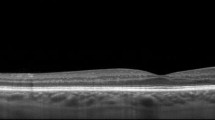

Optic disc pit maculopathy (ODP-M) on MHz-OCT. Fundus photograph, comprehensive en face MHz-OCT reconstruction and three serial sections through the ODP and adjacent retina by MHz-OCT showing the course of the pit cavity along the outer border of the pre- and retrolaminar optic nerve and all pathologic characteristics of ODP-M (retinoschisis, atrophy of inner retinal layers, serous macular detachment, intrapapillary proliferation) (a) Fundus photograph of the left eye of an 18-year-old man (Pat. 1 in Table 1) (b) Comprehensive en face MHz-OCT image showing ODP-M. The scanned OCT-lines in (C-E) are shown as labeled long green arrows in (b). c MHz-OCT scan with temporal ODP and several schisis cavities between different retinal layers and accumulation of subretinal fluid. d MHz-OCT scan cutting the macula-area, with ILM as roof of the schisis cavity. More schisis cavities in the adjacent outer retinal layers including schisis within the subinternal limiting membrane space, ganglion cell layer, inner nuclear layer, outer nuclear layer, and the subretinal space. e Subpapillary MHz-OCT scan with retinal detachment and subretinal fluid inferior to the fovea. (BCVA 0.6 [dec] (0.2 logMar))

In our study we could demonstrate numerous interconnected schisis cavities in various layers of the retina (Fig. 2), and we believe that fluid can migrate via these schisis cavities. Thus our MHz-OCT findings support a variation of Lincoff’s pattern [27] for the development of ODP-M (Fig. 3). Seen as disease of the vitreoretinal interface [8, 28] in ODP-M a contraction of vitreous fibers could lift and separate the herniated dysplastic retinal tissue inside the pit. This notion has been supported with the fact that MHZ-OCT-imaged intrapapillary proliferations can change significantly over time [26, 29] and seem to correlate with the severity of ODP-M The separation of incarcerated tissue allows an influx of fluid from the pit, leading to a schisis-like inner layer separation [30], which produces a mild centrocoecal scotoma. The liquefied vitreous could be a very likely source for this fluid [31]. Secondly an outer layer hole, often close to the macula, develops beneath the schisis cavity, causing a dense central scotoma. Subsequently an outer layer detachment evolves [2, 27]. This process has also been described for very shallow pits and for membranes spanning over a glaucomatous optic disc [30, 32].